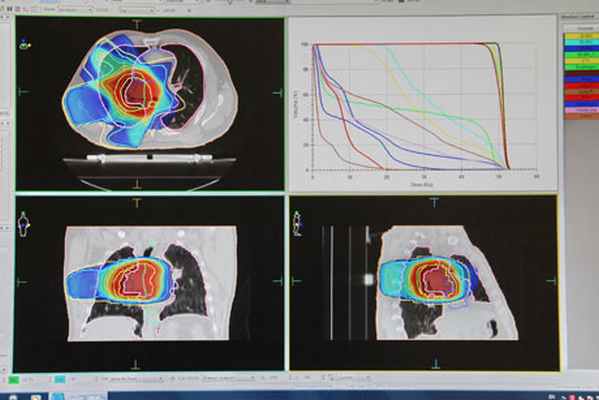

Подготовка к лечению

Лучевая терапия всегда начинается с планирования. Для этого выполняется ряд исследований (рентгенография, УЗИ, компьютерная томография, магнитно-резонансная томография и др.), при которых определяется точное месторасположение новообразования. Врач-радиолог до начала лучевого лечения внимательно изучает историю заболевания, результаты проведенного обследования, осматривает пациента. На основании имеющихся данных врач принимает решение о способе лечения больного и обязательно рассказывает пациенту о планируемом лечении, риске возникновения побочных эффектов и мерах по их профилактике. Ионизирующее излучение является небезопасным для здоровых тканей. Поэтому облучение проводится за несколько сеансов. Количество сеансов определяет врач-радиолог.

Во время сеанса лучевой терапии пациент не испытывает боли и каких-либо других ощущений. Облучение проходит в специально оборудованном помещении. Медицинская сестра помогает больному занять положение, которое было выбрано во время планирования (разметки). С помощью специальных блоков защищают от облучения здоровые органы и ткани. После этого начинается сеанс, который длится от одной до нескольких минут. Врач и медицинская сестра наблюдают за процедурой из кабинета, расположенного рядом с помещением, где проводится облучение.

Как правило, курс дистанционной лучевой терапии длится от 4 до 7 недель (без учета возможных перерывов в лечении). Внутриполостное (и внутритканевое) облучение занимает меньше времени. Существует методика, при которой за один сеанс дают большую дозу, при этом общая доза за курс меньше (при равном эффекте). В таких случаях облучение проводится в течение 3-5 дней. Иногда курс лучевой терапии можно провести амбулаторно, без госпитализации и круглосуточного пребывания в больнице.

Топометрия на аппарате КТ для выбора мишени воздействия

Компьютерное моделирование облучения с учетом окружающих здоровых тканей и органов

Реализация сеанса (сеансов) облучения